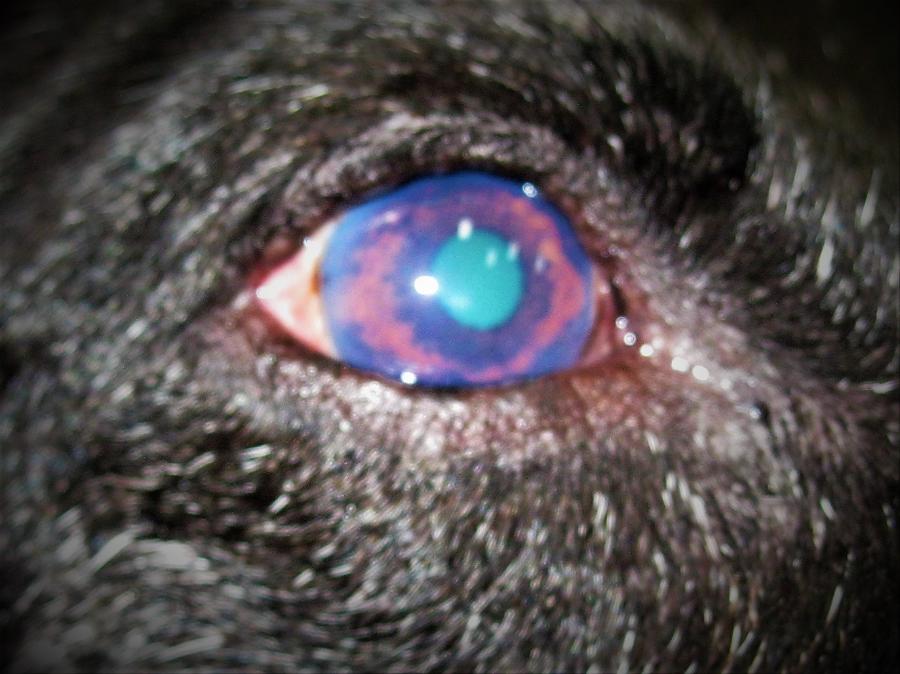

Οφθαλμολογία

Οφθαλμολογία

Το κτηνιατρείο hm vets αναλαμβάνει ψηφιακή ακτινογραφία, έλεγχο δυσπλασίας ισχίου, ορθοπεδική-νευροχειρουργική, χειρουργική μαλακών μορίων, οφθαλμολογία, εσωτερική παθολογία και εργαστηριακές εξετάσεις (αίματος, βιοχημικές, ανοσολογικές, ορμονολογικες, μοριακές και ιστοπαθολογικές).

Το κτηνιατρείο hm vets αναλαμβάνει ψηφιακή ακτινογραφία, έλεγχο δυσπλασίας ισχίου, ορθοπεδική-νευροχειρουργική, χειρουργική μαλακών μορίων, οφθαλμολογία, εσωτερική παθολογία και εργαστηριακές εξετάσεις (αίματος, βιοχημικές, ανοσολογικές, ορμονολογικες, μοριακές και ιστοπαθολογικές).